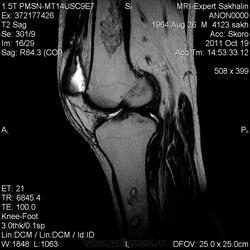

Мужчина с жалобами на боль в коленном суставе.Пришел сразу к нам по направлению врача с подозрением на ДОА, подагрический артрит.Рентгенограмм нет.

Я так понимаю, Вас смущают изменения в диафизах бедренной и большеберцовой костей?

инфаркт костного мозга

- В ранней стадии заболевания - отек (гипоинтенсивный на Т1-взвешенном изображении и гиперинтенсивный на Т2-взвешенном изображении)

- Позднее отграничение вдоль периферии пораженной кости (гипоинтенсивное на Т1 - взвешенном изображении; на Т2-взвешенном изображении - гиперинтенсивная линия по направлению к зоне некроза, соответствует грануляционной ткани)

- Гипоинтенсивная линия по направлению к здоровой кости (склероз, фиброз): признак двойной линии

- Накопление контрастного вещества периферической зоной

- При застарелых инфарктах кости интенсивность сигнала зоны некроза эквивалентна жировой ткани

- Периферическая зона типично извилистая, напоминает гирлянду.

а, b Инфаркт зрелого костного мозга. (а) Сагиттальная протонная плотно-взвешенная МРТ с подавлением МР-сигнала от жировой ткани. Изображение демонстрирует гирляндовидный склеротический край и центральный участок с сигналом жирового костного мозга. Множественные некротические зоны расположены преимущественно в метадиафизальной области, однако несколько находятся непосредственно рядом с суставом, в связи с чем имеется риск уплощения суставных поверхностей;

b) Рентгенологическое исследование демонстрирует выраженный склеротический край и центральный участок снижения рентгенопрозрачности в дистальном отделе бедренной кости и в большеберцовой кости. Проксимальный отдел бедренной кости демонстрирует участок частичного грубого склероза, который иногда трудно отличить от энхондромы.